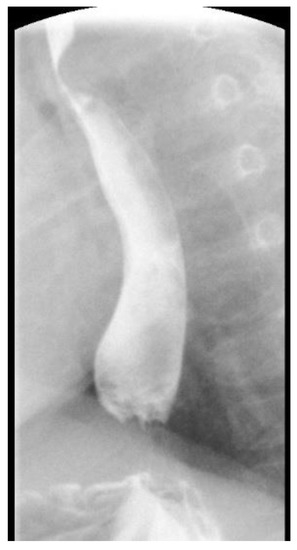

2. Case Report 1